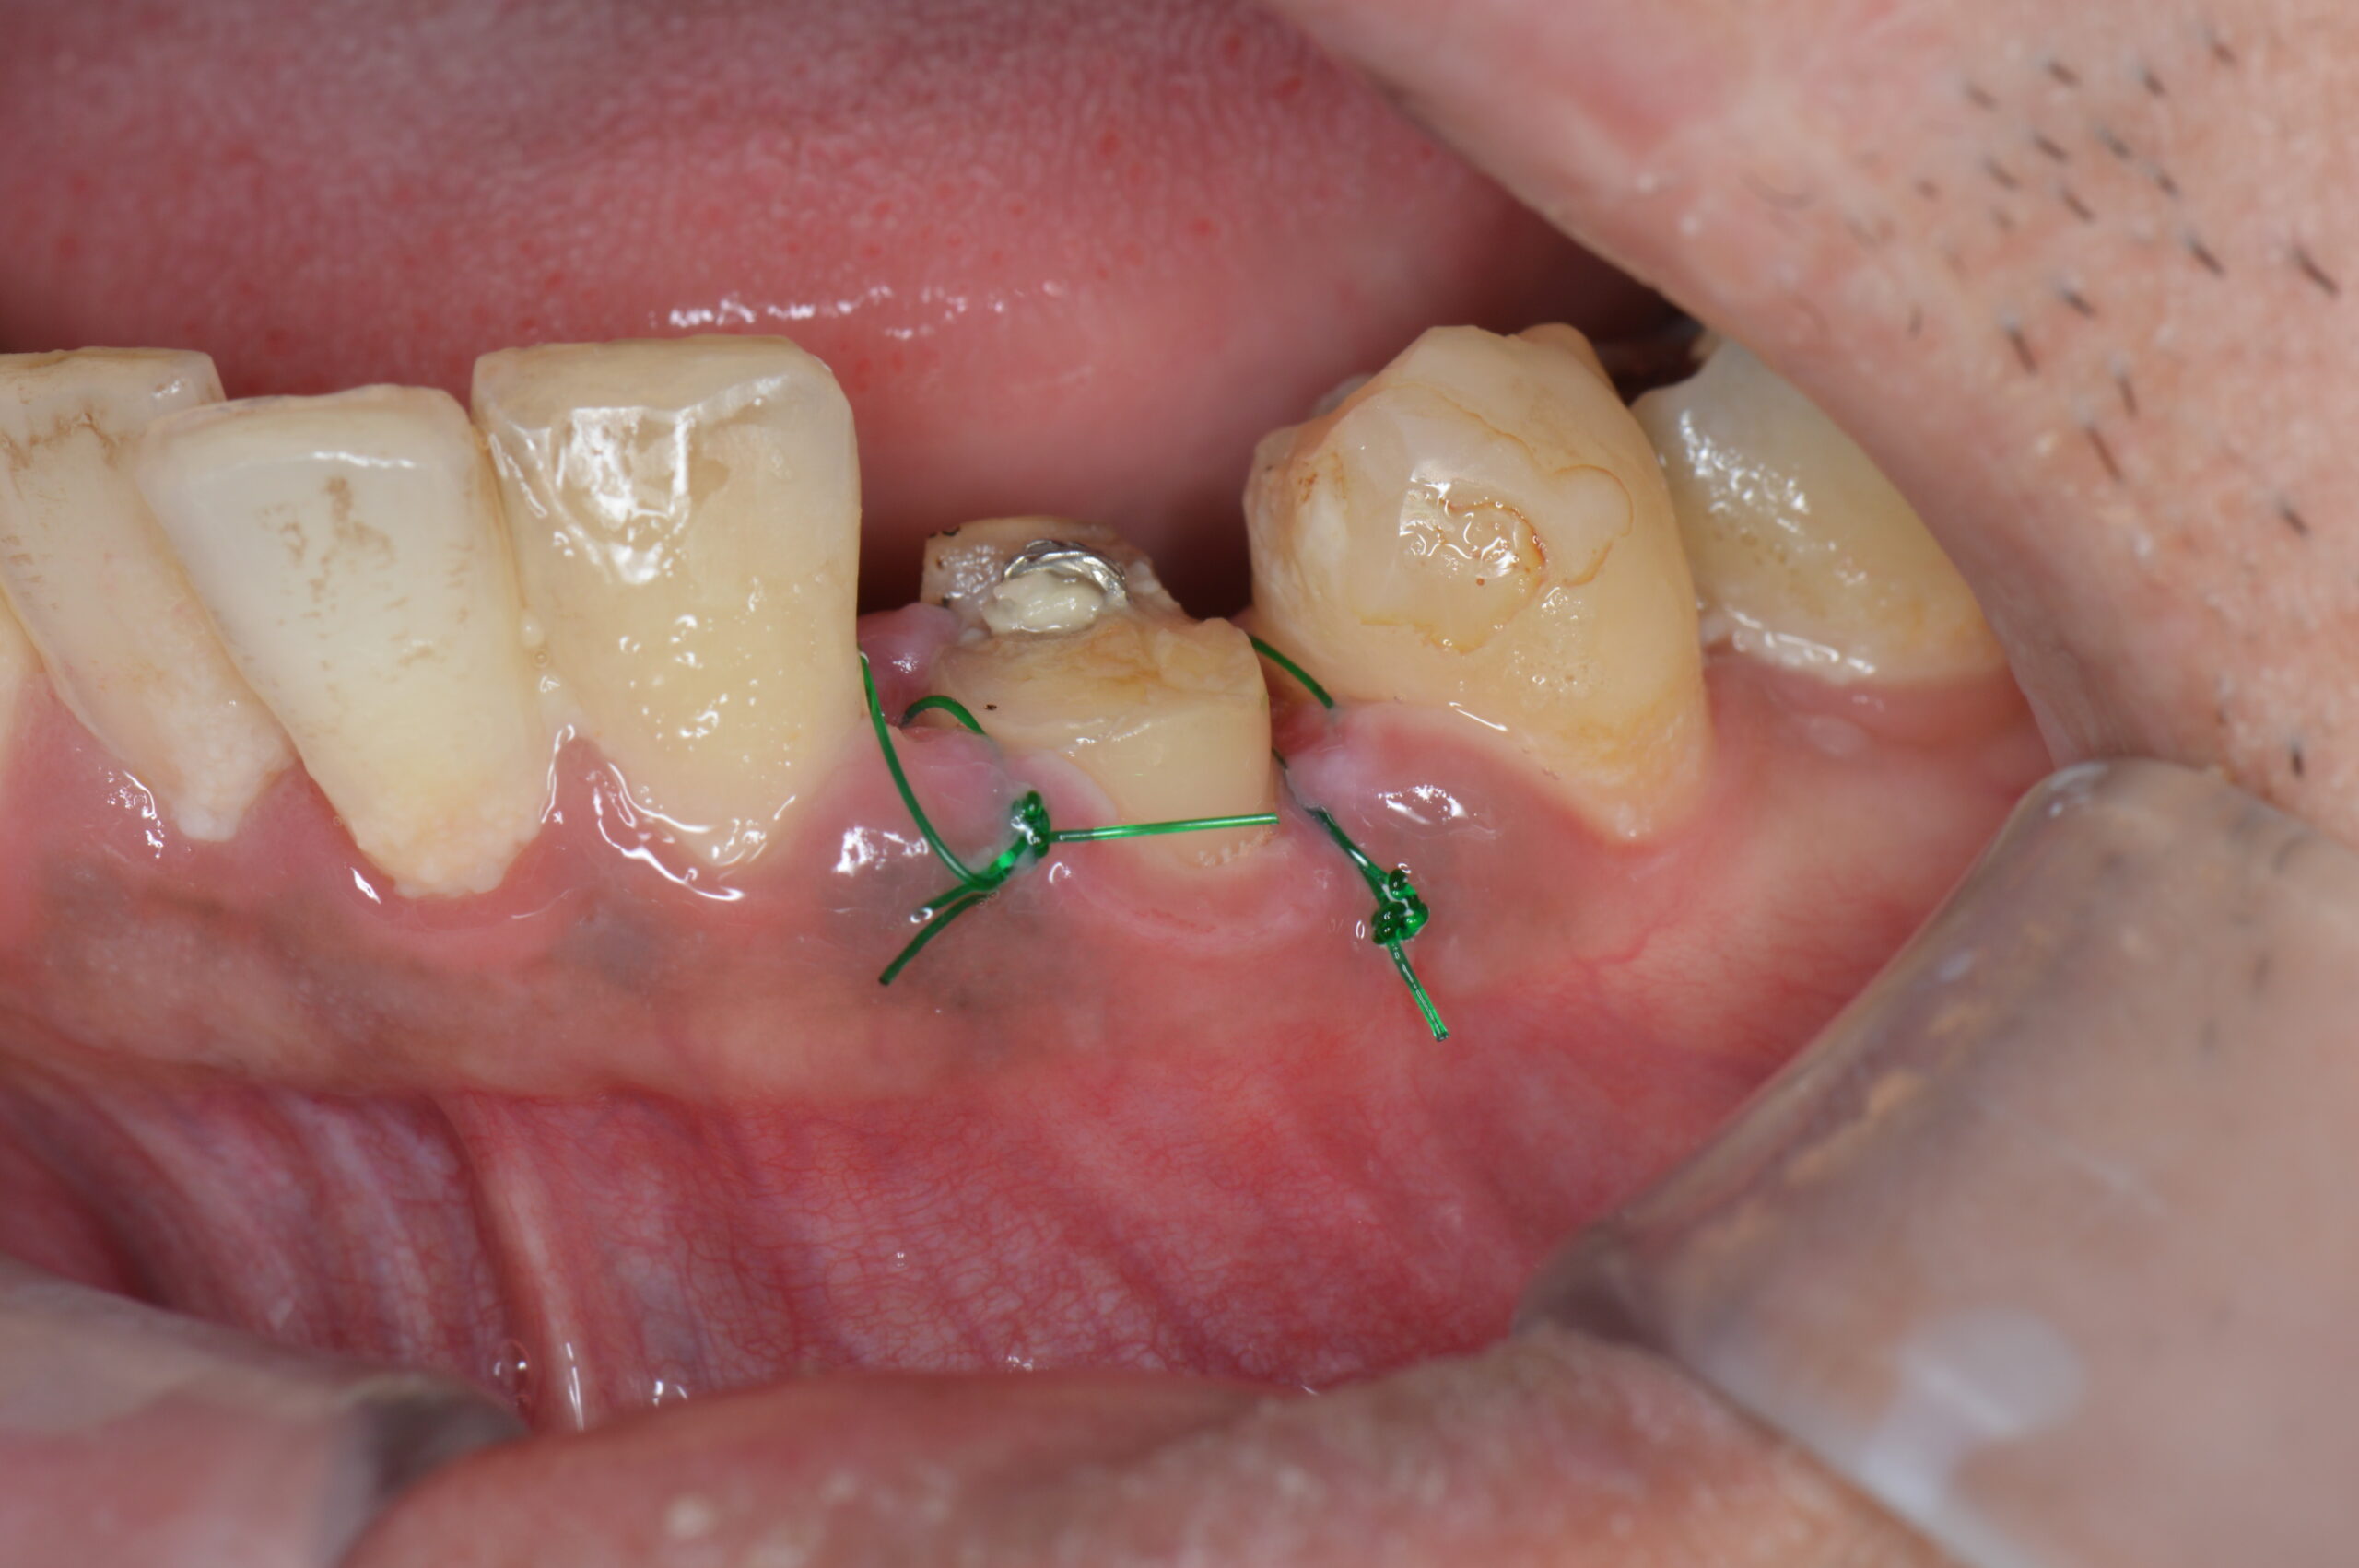

下の写真は、今回ご紹介する患者さんの初診時の口腔内です。事故によって歯が歯肉の際で折れており、歯肉の上に歯質がほとんど残っていない状態です。この状態ではフェルール(被せ物の土台となる歯質の壁)が確保できず、そのまま被せ物を作ることができません。

下の写真は、歯冠長延長術を行った直後の口腔内です。手術によって歯肉の位置が下がり、歯根が歯肉の上に十分に露出しています。これにより、フェルールを確保するための歯質がしっかりと見えるようになりました。